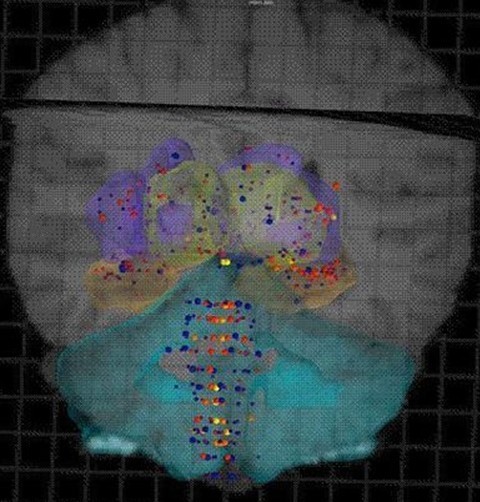

科技日報訊 據美國麻省理工學院出版的《技術評論》雜志4月13日報道,艾倫腦科學研究所的科學家繪制出了兩個迄今最完整的人腦基因圖譜,為神經科學研究提供了重要的數據支撐�?茖W家表示,最新“出爐”的人腦基因圖譜提供的數據將被廣泛用于與帕金森癥、精神分裂癥、多發性硬化癥甚至肥胖等與神經障礙和認知功能有關的疾病的研究,以及探究健康的大腦如何工作。

科學家將相關數據編制成一個名為“艾倫人腦圖譜”的數據庫,該圖譜除了顯著標識出人類基因圖譜中的每個基因在大腦的何處表達之外,還涵蓋了大腦核磁共振成像(MRI)和磁共振彌散張量成像(DTI)提供的數據,供公眾自由免費訪問。這些數據顯示,人腦之間的相似度高達94%,至少82%的人類基因都會在大腦中表達。

與高性能、多功能的全球定位系統(GPS)一樣,艾倫人腦圖譜確定了人腦中的1000個解剖點,指明了每個點上特定的基因表達和基本的生物化學特性。科學家能借用艾倫人腦圖譜探測人腦,厘清人腦遭受的疾病和損傷(包括生理損傷和精神健康疾�。⿲Υ竽X特定區域的影響�?茖W家有望借此準確定位出某種特定的藥物應作用于大腦的哪個區域并最終更好地控制很多療法的治療結果。